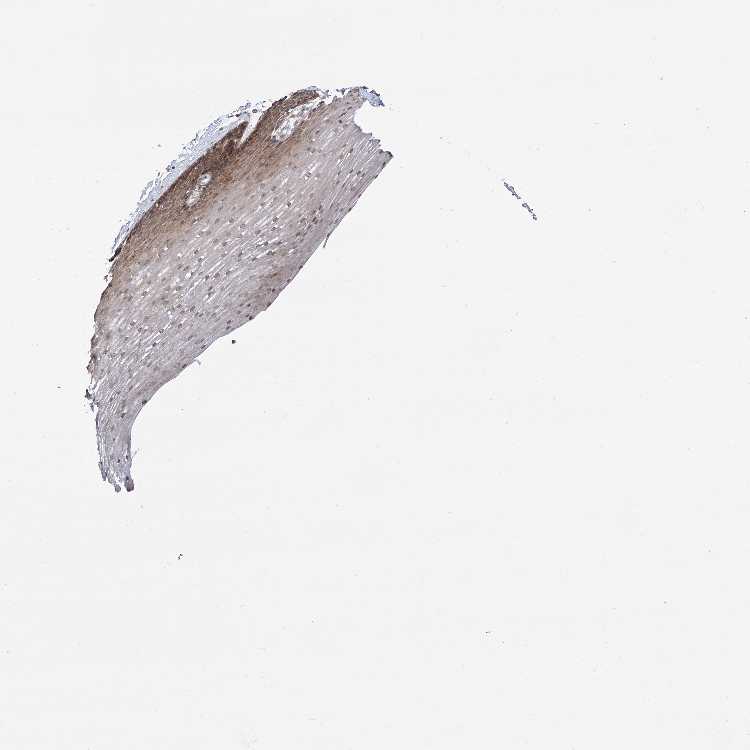

ESOPHAGUS - Antibody stainingi

Antibody staining in the annotated cell types in the current human tissue is reported as not detected, low, medium, or high, based on conventional immunohistochemistry profiling in selected tissues. This score is based on the combination of the staining intensity and fraction of stained cells.

Each image is clickable and will lead to virtual microscopy that enables deeper exploration of all samples and also displays staining intensity scores, fraction scores and subcellular localization as well as patient and tissue information for each sample.

Antibody HPA043918Antibody HPA064397Antibody CAB029995

Squamous epithelial cells HighMediumMedium